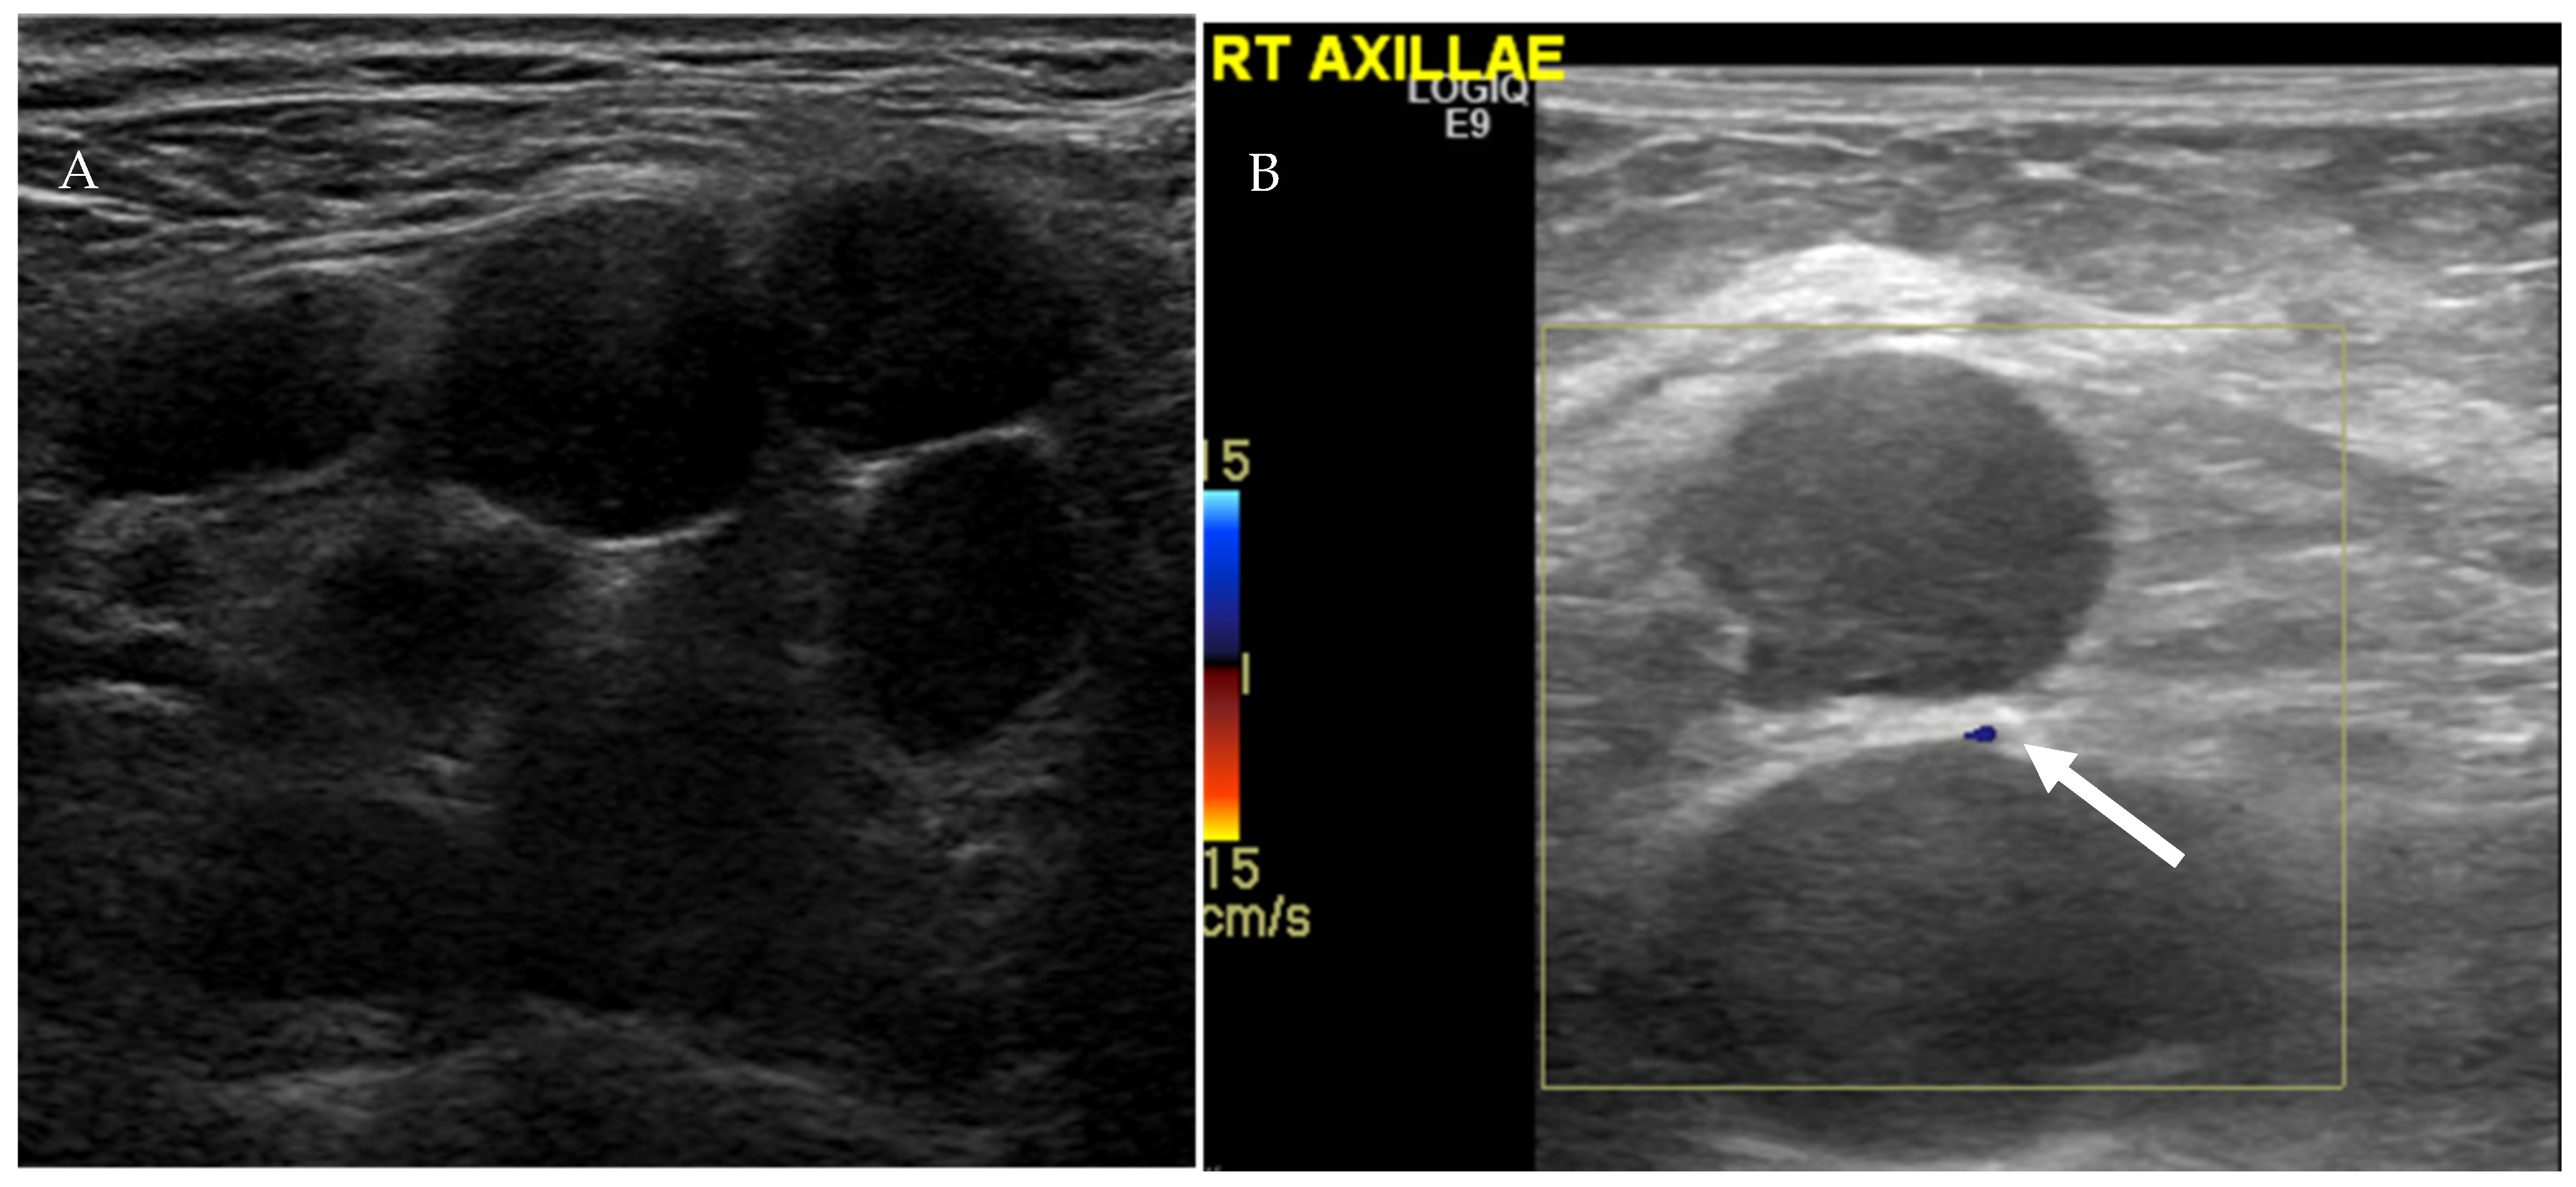

4.1.1. Ultrasound Evaluation of the Lymphatic System

- Prativadi, R.; Dahiya, N.; Kamaya, A.; Bhatt, S. Chapter 5 Ultrasound Characteristics of Benign vs Malignant Cervical Lymph Nodes. Semin. Ultrasound CT MRI 2017, 38, 506–515. [Google Scholar] [CrossRef]

- Dudea, S.M.; Lenghel, M.; Botar-Jid, C.; Vasilescu, D.; Duma, M. Ultrasonography of superficial lymph nodes: Benign vs. malignant. Med. Ultrason. 2012, 14, 294–306. [Google Scholar]

| US Criteria | Benign Lymph Node | Malignant Lymph Node |

|---|---|---|

| Size | <1 cm in short axis | ≥1 cm in short axis |

| Shape | Oval or elliptical | Round |

| Border | Indistinct | Sharp |

| Echogenicity | Hypoechoic | Very hypoechoic |

| Hilum | Maintained fatty hilum | Absent fatty hilum |

| Vascularity | Avascular or hilar vascularity | Peripheral or mixed |

| Resistive index | Low | High |